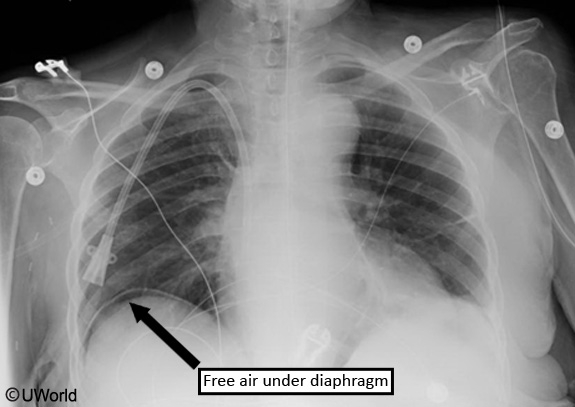

Plain films of the abdomen are typically normal in acute mesenteric ischemia, but are sometimes warranted to exclude a perforated viscus and free air under the diaphragm.

This patient with acute-onset severe abdominal pain, fever, tachycardia, and signs of peritonitis (eg, guarding, rigidity, reduced bowel sounds, rebound tenderness) likely has a perforated viscus. Her preceding episodic epigastric pain, nausea, history of NSAID and alcohol use, and positive stool guaiac test raise suspicion for peptic ulcer disease as the cause of perforation. The diagnosis of gastrointestinal perforation is confirmed with upright x-ray of the chest and abdomen, which typically shows free intraperitoneal air under the diaphragm (pneumoperitoneum).